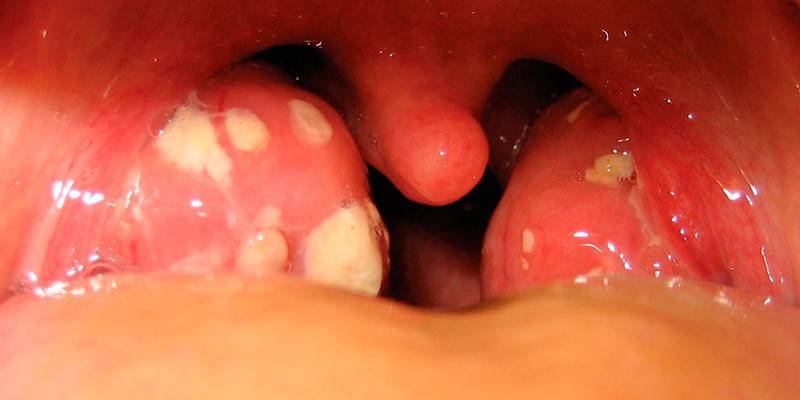

- Com amigdalite estreptocócica (angina), faringite e outras infecções bacterianas do trato respiratório - febre, sinais de intoxicação geral grave, danos às membranas mucosas.

O Streptococcus agalactia é encontrado em um esfregaço da vagina, uretra ou reto, que pode ser prescrito quando a flora cocal é detectada em um exame de urina.Depois de examinar o biomaterial por microscopia de laboratório, uma cultura é realizada em um meio de cultura que ajuda a identificar com precisão o tipo de infecção bacteriana, o grau de concentração de microorganismos e sua resistência a drogas antibacterianas.